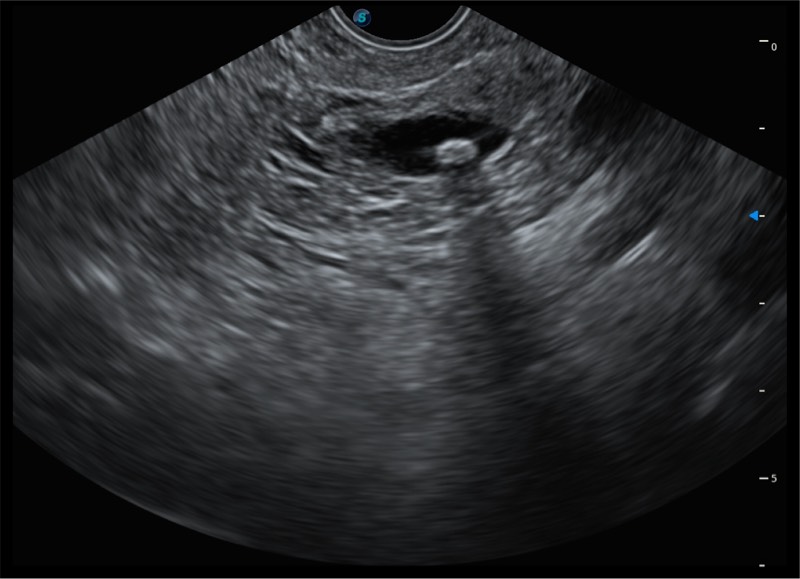

搭载百万级CMOS成像技术

及自主研发凸阵换能器,

可呈现优质的内镜和超声画面